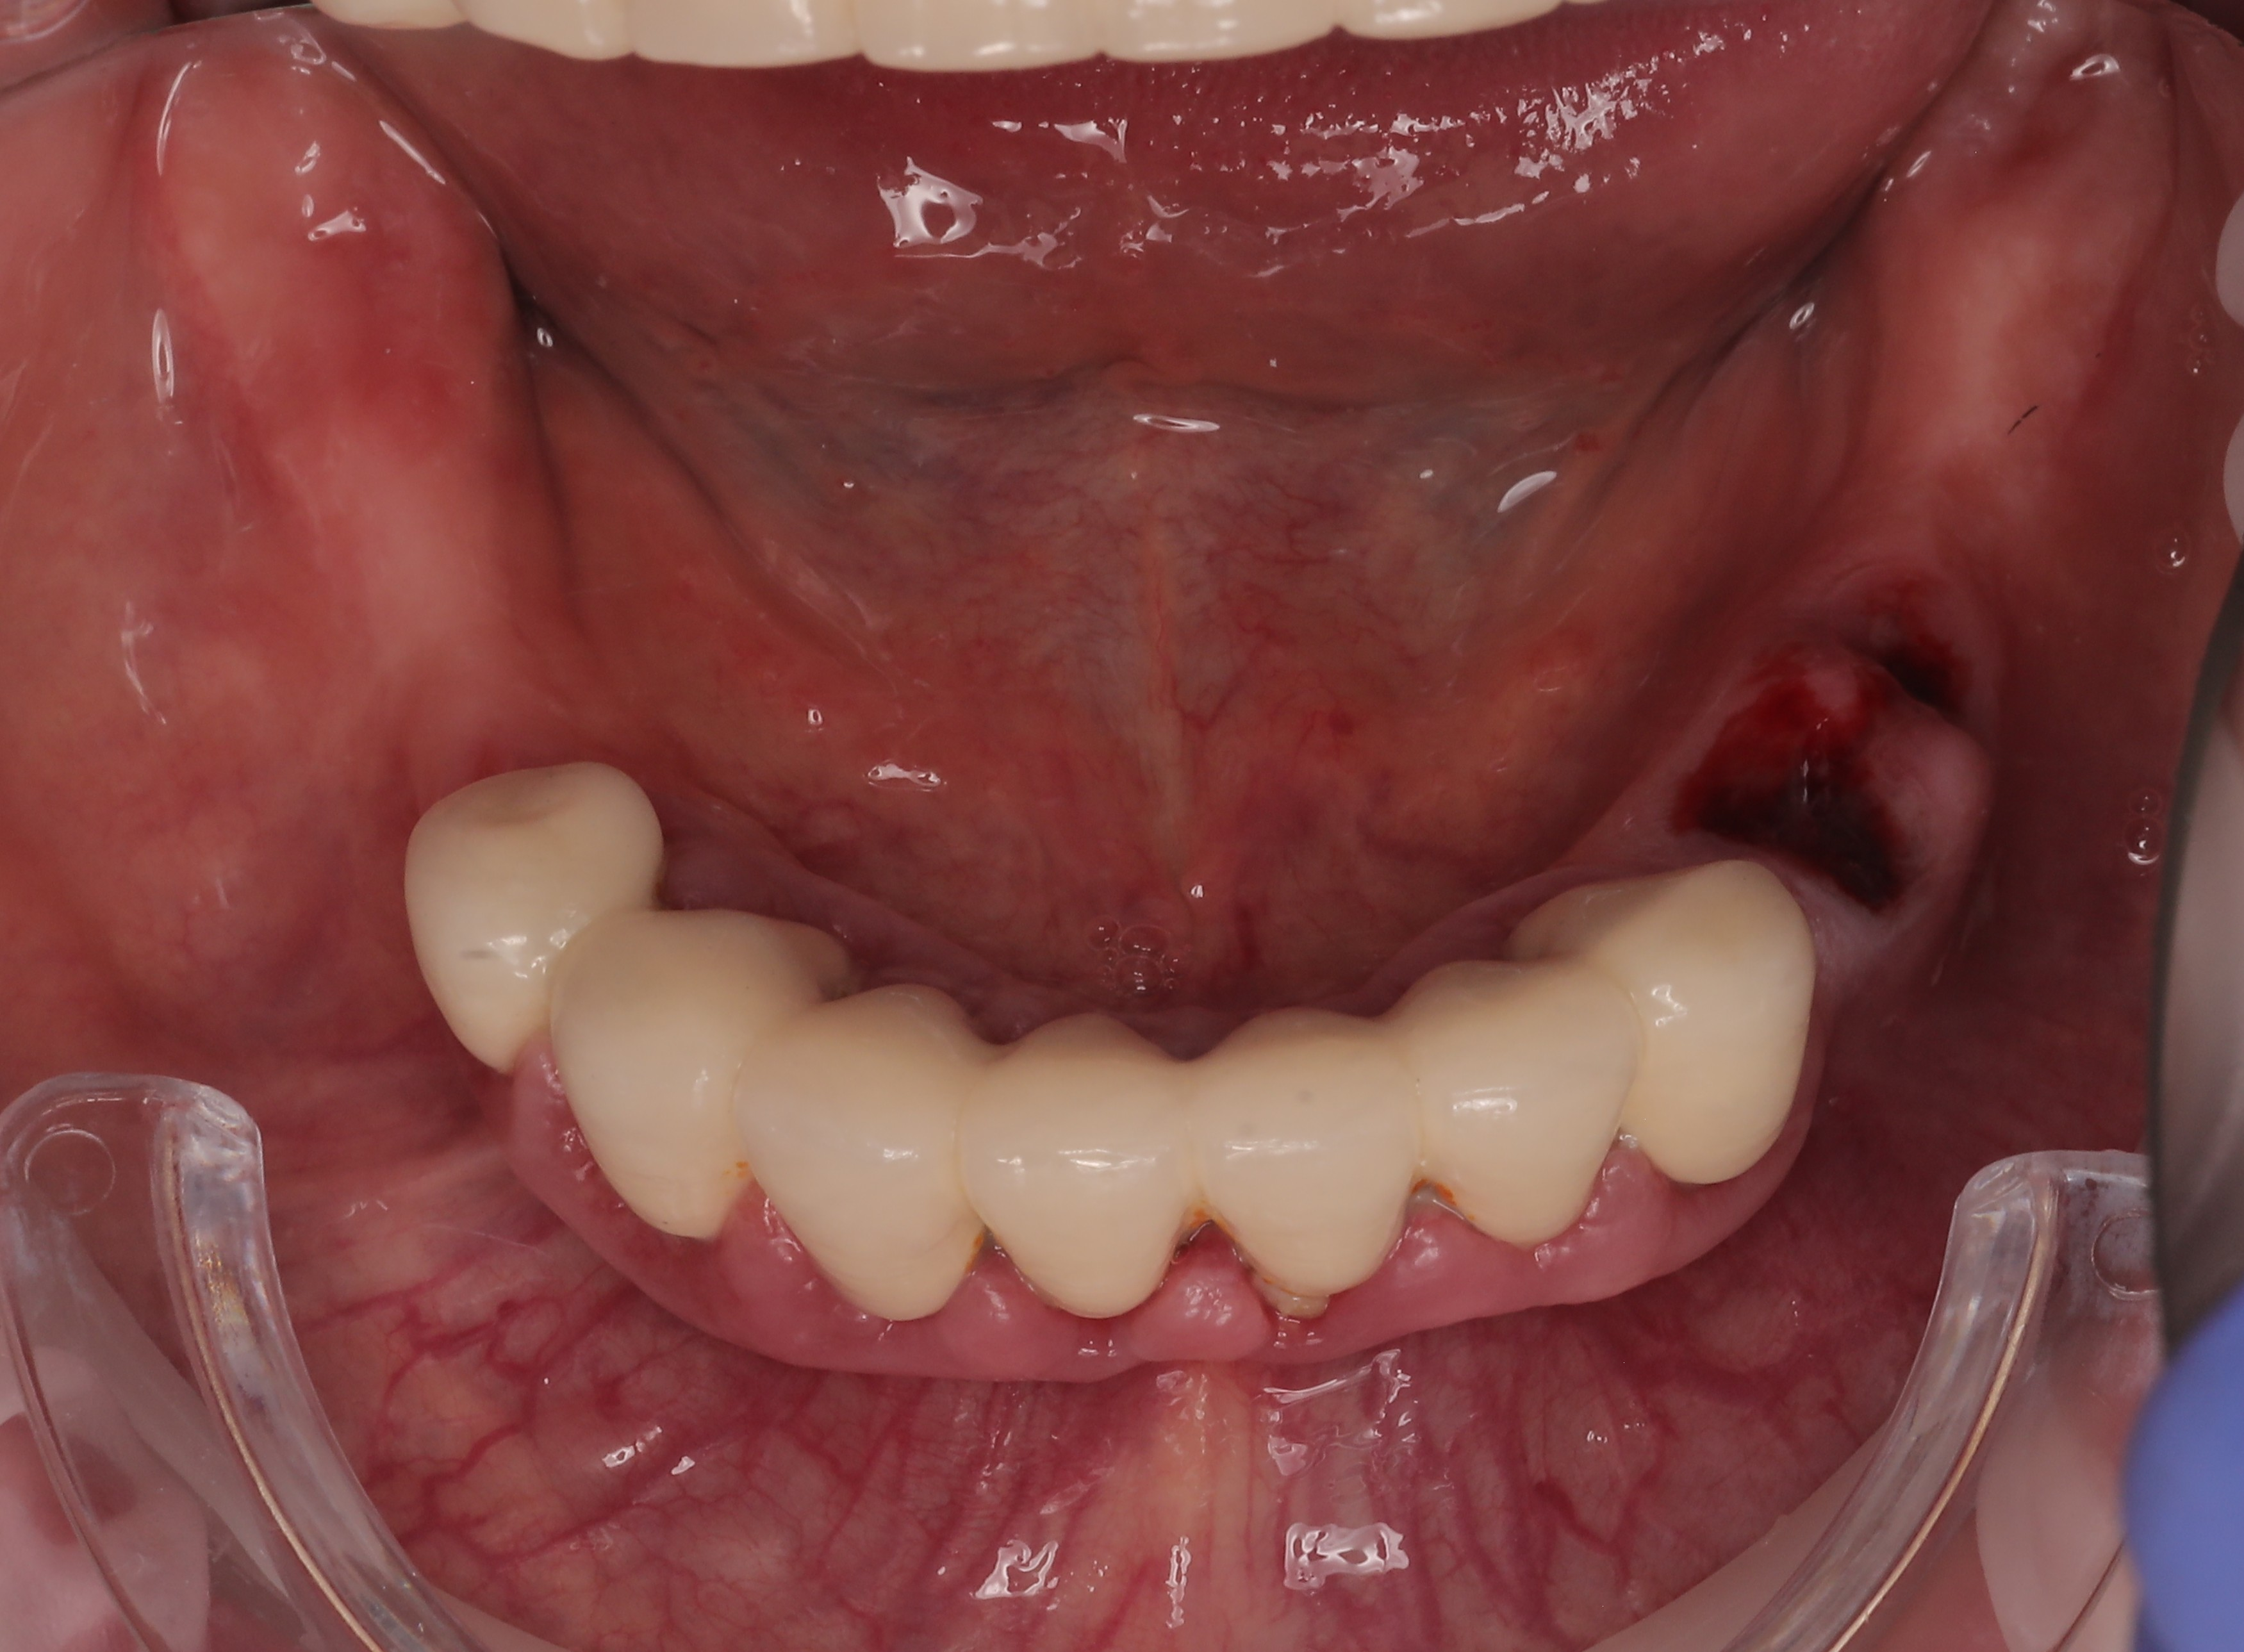

Mandibular :

Following marker placement and necessary bone reduction, JDental Icon Plus implants were installed and fitted with Multi-Unit Abutments (MUA). A preliminary suturing was performed to stabilize the site, after which a mandibular IPG scan was executed to capture precise implant positions. The procedure was finalized with the complete closure and suturing of the gingival grafts to ensure optimal soft tissue healing.